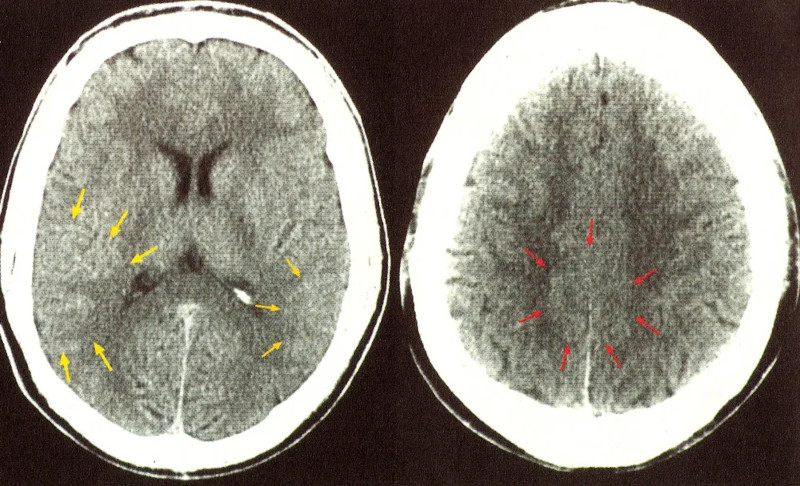

Si tratta di immagini presenti nel contesto della massa cerebrale, ma anche in altre aree corporee e sono la visualizzazione di relè di attivazione organica che vengono chiamati in causa quando si verifica una DHS. La radiologia ufficiale indica questi FH come artefatti. A seconda della fase biologica in cui si trovano, questi focolai hanno aspetti diversi. Nella Fase attiva la visualizzazione è di cerchi concentrici ben definiti. Una volta avvenuta la Conflittolisi e con la edemizzazione del FH, i margini di visualizzazione divengono più indefiniti. Con la guarigione completa il FH mostra un aspetto biancastro ad indicare un ispessimento della glia periferica.